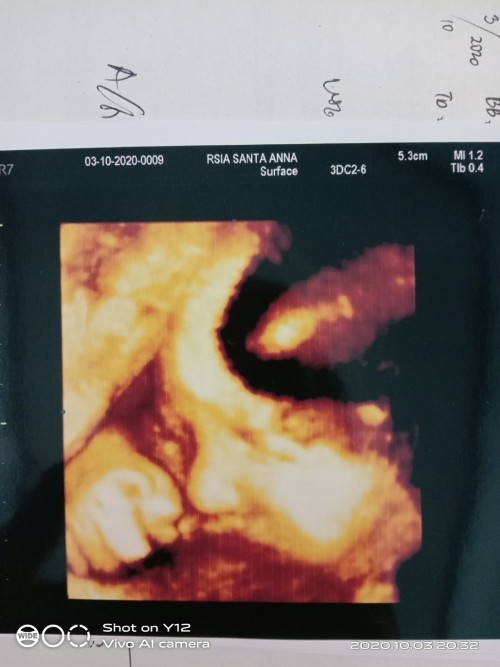

Ini fto baby ku......

baby ku 36week 🤗😘